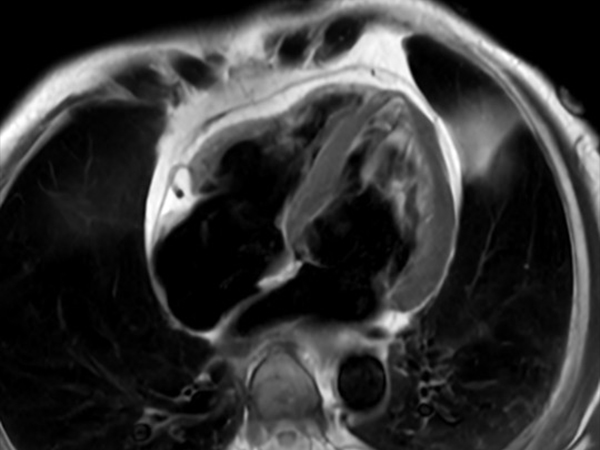

Comprehensive Cardiac with SmartSpeed Precise